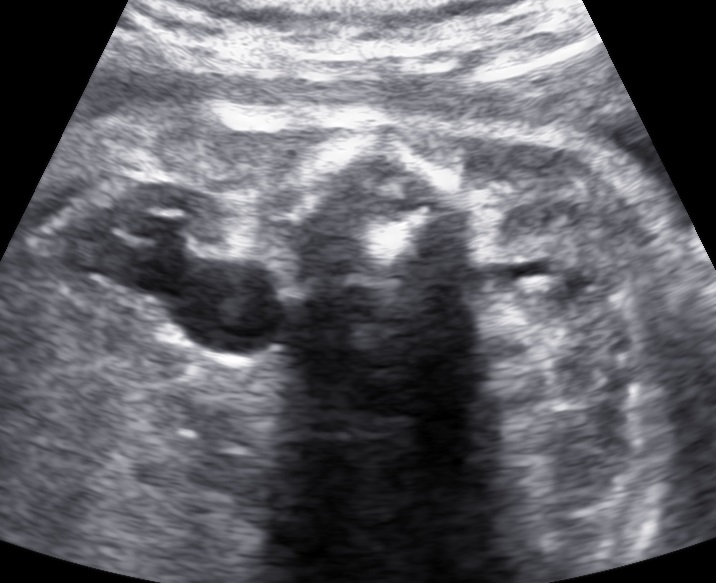

The gestational week does not influence the diagnosis of polyhydramnios. The size of the uterus could be suggesting of this condition, however the diagnosis should be made during ultrasound examination. There are two common ways to estimate the volume of the amniotic fluid:

- Single Deepest Pocket (SDP). A vertical measurement in the deepest amniotic fluid pocket. Values below 2 cm indicate oligohydramnios, values over 8 cm indicate polyhydramnios (8-11: mild, 12-15: moderate, > 16: severe). In multiple gestation, a range of 3–8 cm is defined as normal. Another technique is the

- Amniotic Fluid Index (AFI). This is the sum of vertical measurements of all four quadrants (polyhydramnios usually >24).